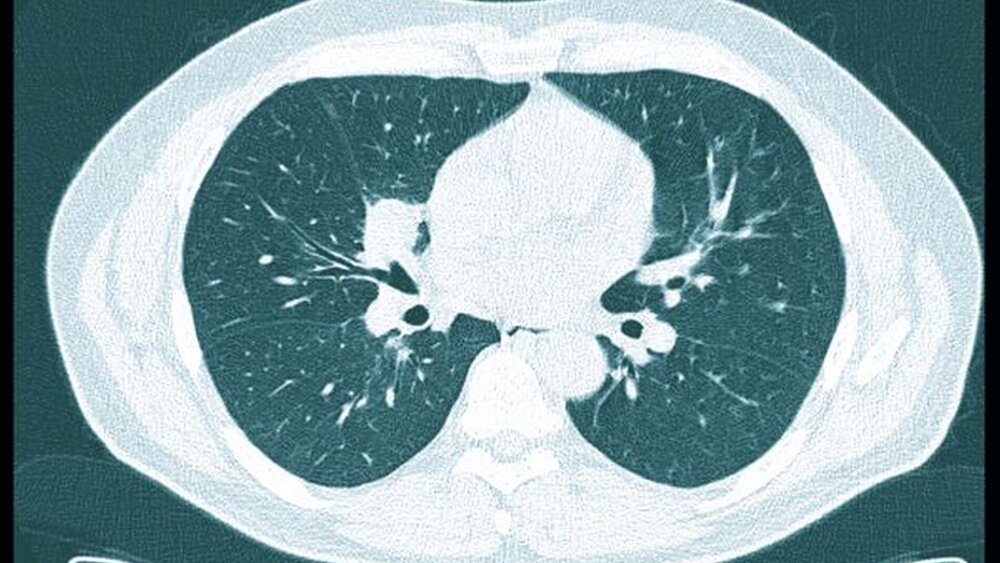

Die weitergehende laborserologische Diagnostik bestätigte die Wegener Granulomatose durch das Vorhandensein von c-ANCA (AntiNeutrophile Zytoplasmatische Antikörper). Die Urindiagnostik zeigte eine geringe glomeruläre Erythrozyturie. Die veranlasste Computertomographie des Thorax beschrieb intrapulmonale Rundherde, vereinbar mit Granulomen bei einem Morbus Wegener (Abbildung 5).

Der Morbus Wegener beschreibt eine systemische Erkrankung, die durch eine nekrotisierende, granulomatöse Entzündung des oberen und des unteren Respirationstrakts, eine Glomerulonephritis und eine Vaskulitis kleiner und mittelgroßer Gefäße charakterisiert ist [Ponniah et al., 2005]. Der Krankheitsverlauf variiert zwischen milden, auf den Respirationstrakt beschränkten Symptomen und einem schweren Verlauf mit rascher Progredienz und lebensbedrohlichem Multiorganversagen. Bei über 80 Prozent der Patienten manifestieren sich die Symptome im Kopf-Hals-Bereich. So klagen die Patienten, wie auch im eigenen Fall geschildert, in der Initialphase unter anderem über eine persistierende Rhinorrhoe, eine Schmerzsymptomatik im Nasennebenhöhlenbereich, orale und nasale Ulzera sowie über Ohrenschmerzen bedingt durch Mittelohrergüsse [Gottschlich et al., 2004]. Ein Befall der Lunge mit Dyspnoe, Hämoptysen und den in der Bildgebung charakteristischen Granulomen ist häufig. Im weiteren Verlauf (Generalisationsstadium) kann es zu einem Befall der Nieren (Glomerulonephritis), der Gelenke (Arthralgien) oder auch der Augen (Episkleritis) kommen. Häufig geht die Erkrankung mit einer Reduktion des Allgemeinbefindens (Fieber, Nachtschweiß, Abgeschlagenheit und Gewichtsverlust) einher [Gottschlich et al., 2004].

Die Diagnostik des Morbus Wegener wird aus der Synopsis von Klinik, Histopathologie und Serologie entsprechend den Kriterien des „American College of Rheumatology“ (ACR, Tabelle) gestellt. Dabei müssen mindestens zwei dieser vier Kriterien erfüllt sein. Im eigenen Fall waren dies der nekrotischulzerierende Befund im Gingiva- und im Nasennebenhöhlenbereich, die Granulome im CT-Thorax sowie die Mikrohämaturie bei der Urin diagnostik.